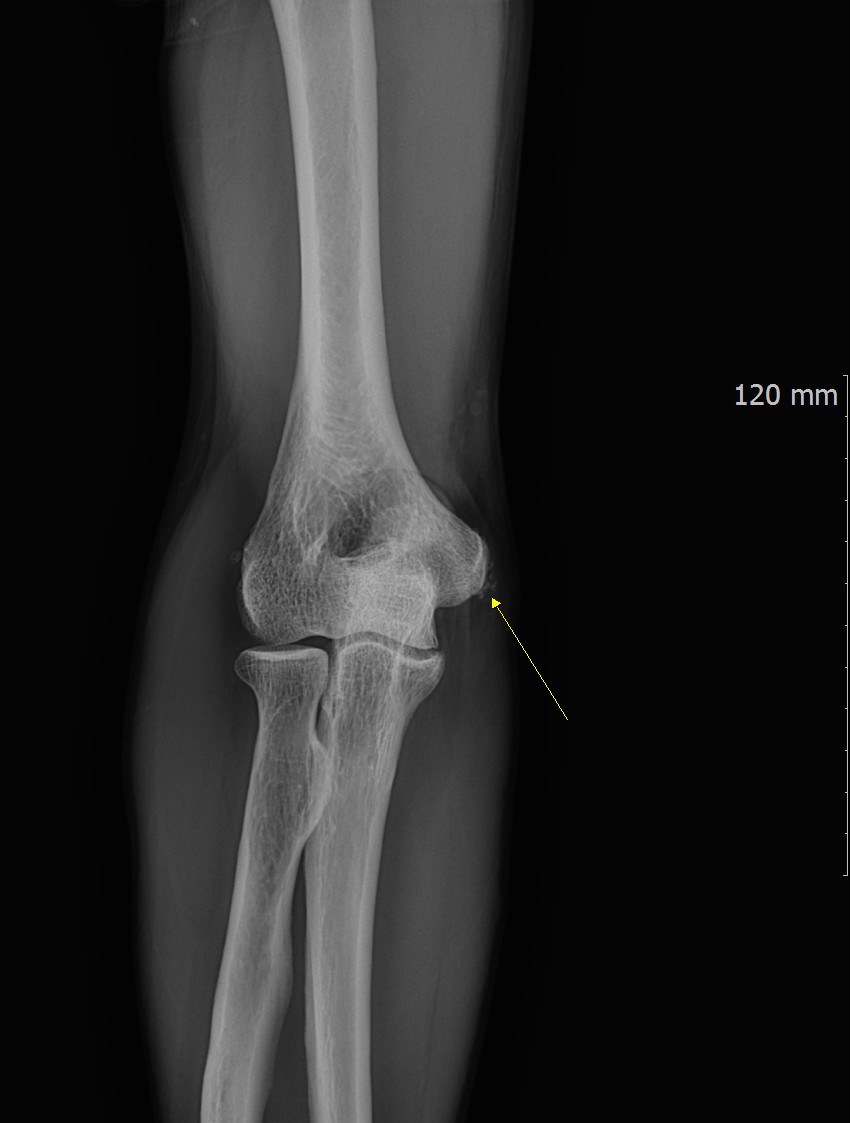

One advantage of calcific tendinopathy is that diagnosis is usually straightforward.

X-ray imaging can clearly visualize calcium deposits within soft tissue or tendon structures.